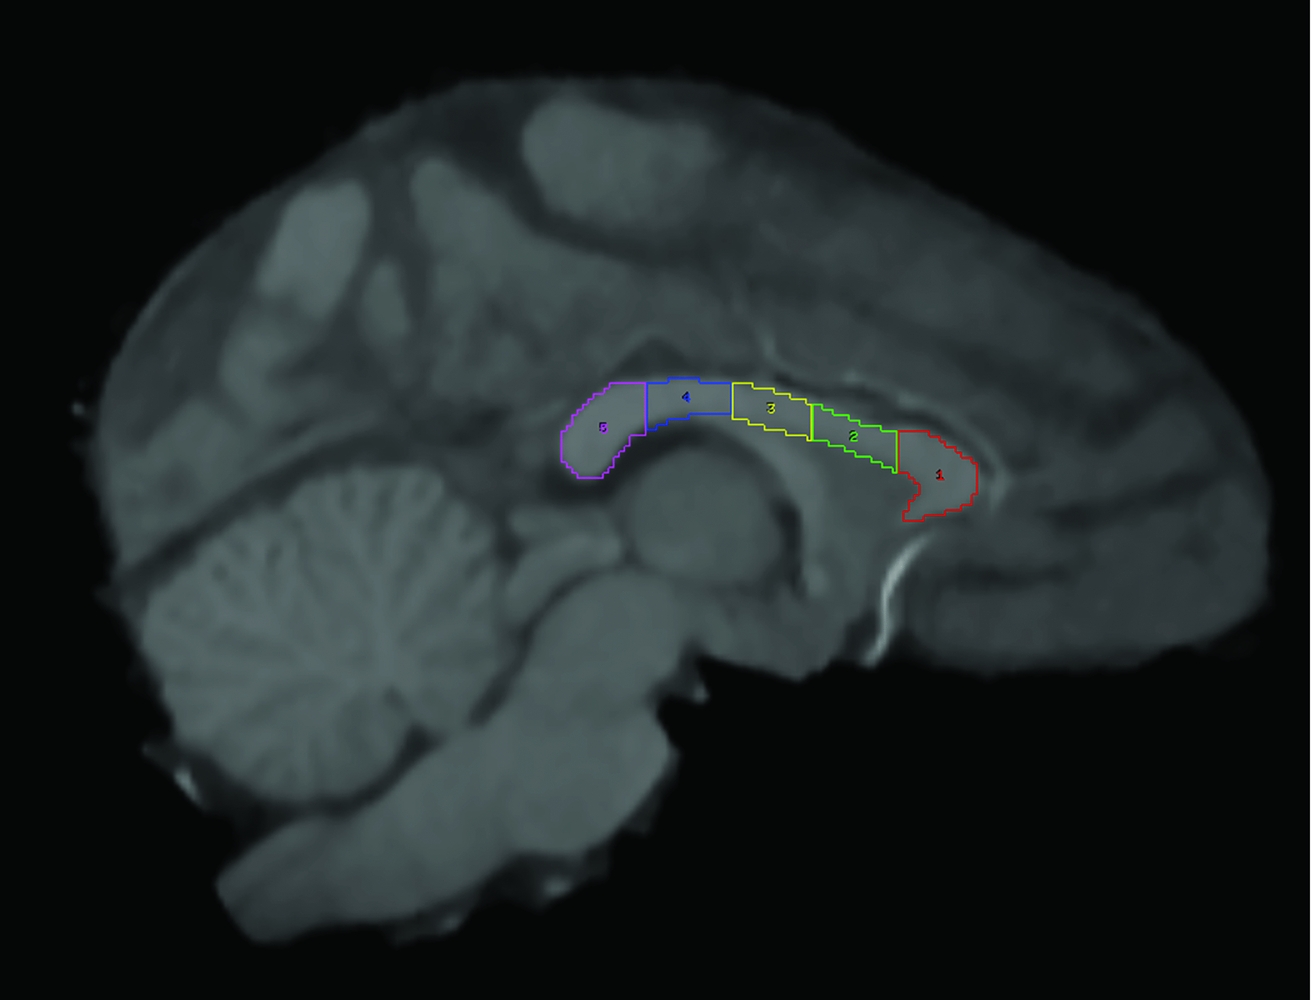

Measurements of CC area were then performed from the midsagittal section, where the CC can be readily identified, using methodology originally described by Biegon and colleagues (Biegon et al., Reference Biegon, Eberling, Richardson, Roos, Wong, Reed and Jagust1994), and later adapted to nonhuman primates (Sanchez et al., Reference Sanchez, Hearn, Do, Rilling and Herndon1998). In the original procedure, the anterior 20% of the CC was defined as the genu, the posterior 20% defined as the splenium, and the middle 60% defined as the body. In adapting this to nonhuman primates, Sanchez et al. (Reference Sanchez, Hearn, Do, Rilling and Herndon1998), Phillips et al. (Reference Phillips, Sherwood and Lilak2007), and Pierre et al. (Reference Pierre, Hopkins, Taglialatela, Lees and Bennett2008), further delineated the body into three equal regions: anterior midbody, medial midbody, and caudal midbody. These subdivisions of the CC are believed to correspond to functional connectivity with cortical areas (Aboitiz et al., Reference Aboitiz, Scheibel, Fisher and Zaidel1992; Alexander et al., Reference Alexander, Lee, Lazar, Boudos, Dubray, Oakes, Miller, Lu, Jeong, McMahon, Bigler and Lainhart2007; Hofer & Frahm, Reference Hofer and Frahm2006). The anterior region of the genu and anterior midbody connects higher-association areas of the frontal lobe; the medial and caudal midbody connect primarily sensorimotor regions; the posterior region of the splenium integrates visuospatial regions of the cortex. Analyze 10.0 (Mayo Foundation for Medical Education and Research) was used to divide and measure the midsagittal area of the CC in mm2. To subdivide the CC, the entire length of the CC was first manually traced, then divided into five equally spaced sections (see Figure 2). Two individuals (KAP and EAB) performed measurements of the CC; there was a high degree of concordance in measures, r = .88. Details on the measurements of total CC area and CC subdivision area were provided in Phillips and Kochunov (Reference Phillips and Kochunov2011). Regional development rates were estimated by fitting a linear regression to the dataset consisting of both in-utero and postnatal data points. In this way we estimated mm2/week of development in callosal subdivisions.

FIGURE 2 Anatomical subdivision of the baboon corpus callosum from MRI sagittal view. The total midsagittal area was divided into five equally spaced subdivisions. 1 = genu; 2 = anterior midbody; 3 = medial midbody; 4 = caudal midbody; 5 = splenium.